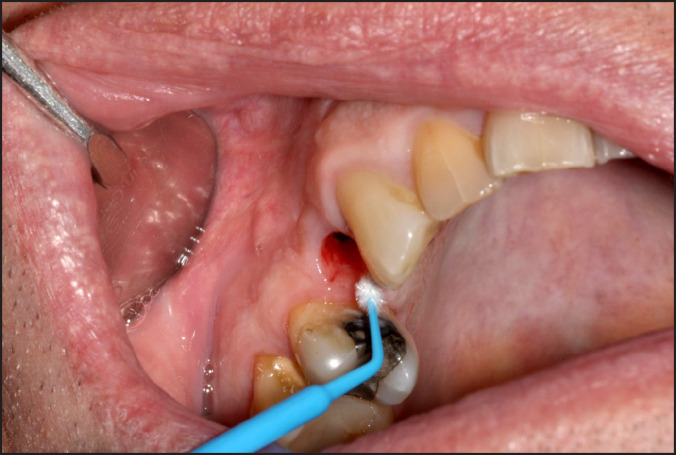

Material and methods: Ten patients with a single implant supported prosthesis connected to zirconia or titanium abutments were invited at the five-year control. A clinical examination and a survey on experience of function and appearance were conducted. A mucosa biopsy taken in close vicinity to the implant were analysed by real-time polymerase chain reaction (qPCR) and presence of particles in a scanning electron microscope/energy-dispersive X-ray spectroscope (SEM/EDX). Cytological smear samples were collected and analysed through inductively coupled plasma mass spectrometry (ICP-MS) to investigate presence of particles on implant heads.